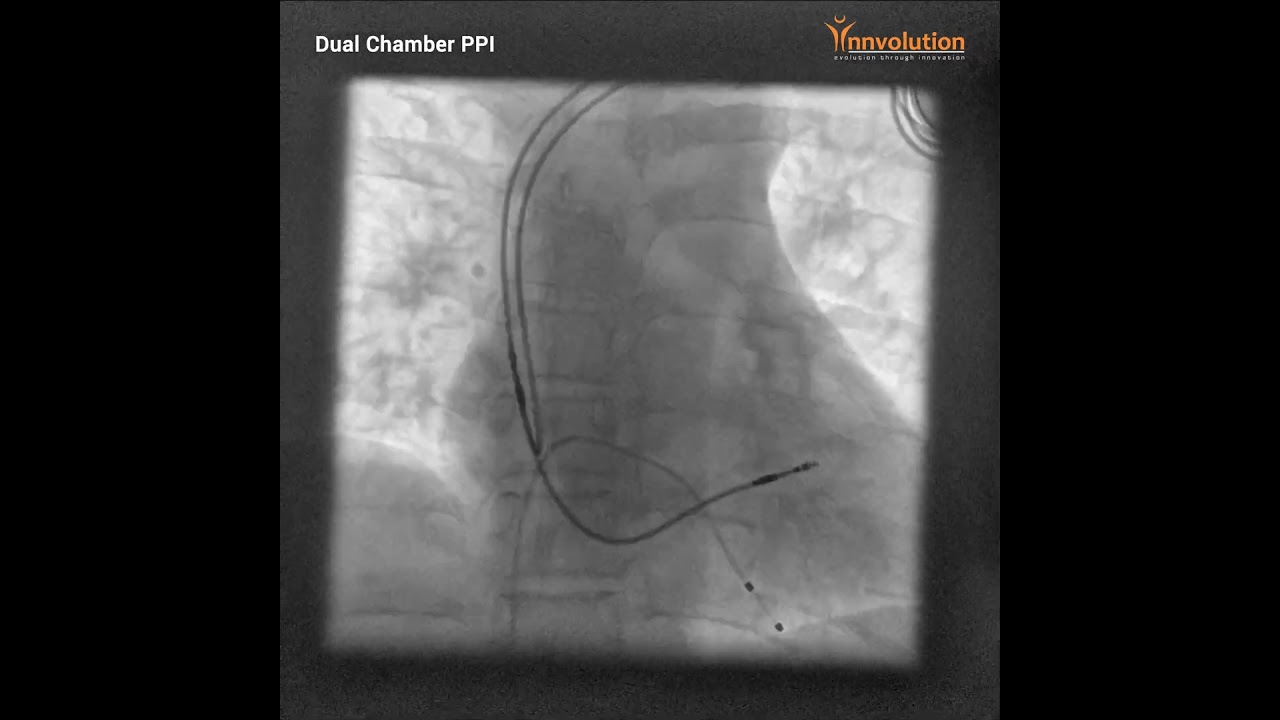

Dual Chamber PPI

A successful Dual Chamber PPI procedure was recently performed on a 48-year-old female with complete heart blockage in our state-of-the-art Premier Elite Cathlab. Our Premier Cathlab's unique +/- 120-degree gantry movement offers unparalleled space optimization, making the implantation of arrhythmia-related devices remarkably efficient.

Pacemaker insertion is a groundbreaking procedure that plays a vital role in regulating abnormal heart rhythms, greatly improving the quality of life for individuals with cardiac conditions. During this procedure, a small device is surgically placed beneath the skin near the collarbone. This device emits electrical signals, ensuring the heart maintains a steady and healthy rhythm.